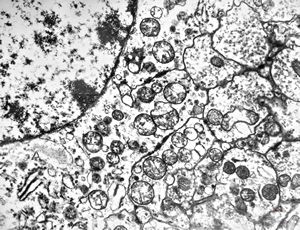

F,50y. | progressive multifocal leukoencephalopathy- viral particles in a glial cell